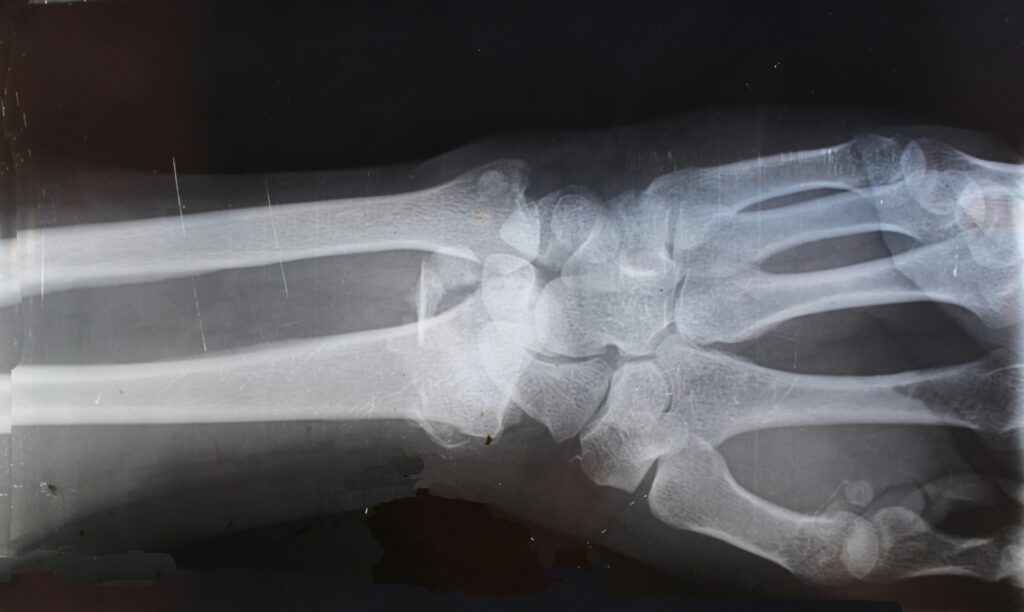

Κάταγμα Κάτω Άκρου Κερκίδας (Colles’ Fracture)

Τι είναι το Κάταγμα Κάτω Άκρου Κερκίδας (Colles’ Fravture); Το κάταγμα Colles είναι ένα υπερέκτασης τύπου κάταγμα της περιφερικής κερκίδας, που συνήθως προκαλείται από πτώση με έκταση του χεριού (FOOSH – Fall On Outstretched Hand).Πρόκειται για το συχνότερο κάταγμα του άνω άκρου, ιδιαίτερα σε ηλικιωμένους με οστεοπόρωση, αλλά και σε νεαρούς αθλητές. Συχνότητα 50+ Γυναίκες […]